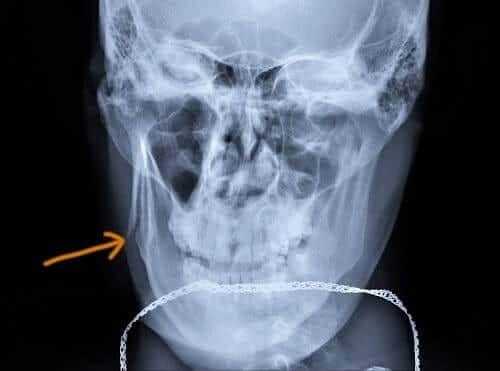

- понтинном, протекающим с полной или частичной утратой мимики, лагофтальмом, свисанием угла рта на одной половине лица;

Наряду с двигательными нарушениями полиомиелитоподобные заболевания сопровождаются болевым синдромом, типичным также для полиомиелита. Отличительной особенностью болей является их мышечный характер. Иногда они имеют нетипичную для полиомиелита локализацию, например — в околопупочной области, в жевательной мускулатуре. Мышечная слабость в паретичных конечностях сочетается с гипотонией и гипотрофией, снижением сухожильных рефлексов. При понтинной форме возникает периферический парез лицевого нерва — слабость мимической мускулатуры, приводящая к перекосу лица в здоровую сторону. В редких случаях отмечаются бульбарные расстройства.